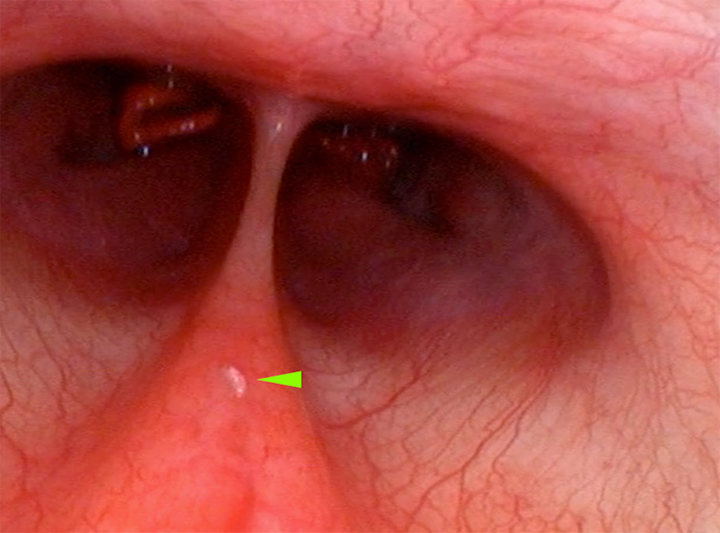

Como ya se ha especificado anteriormente, Oestrus sp. es un parásito que afecta principalmente a la vía aérea alta, por lo que se completó la exploración endoscópica de la paciente con la realización de una exploración endoscópica reglada de vías aéreas altas, en la que se confirmó la existencia de una única forma larvaria a nivel de la nasofaringe (Fig. 4). El estudio rinoscópico rostral descartó la existencia de formas parasitarias a nivel de ambas cavidades nasales.

<p>Confirmación endoscópica de la existencia a nivel nasofaríngeo de L1 de <em>Oestrus</em> sp. en el mismo paciente (punta de flecha verde).</p>

Confirmación endoscópica de la existencia a nivel nasofaríngeo de L1 de Oestrus sp. en el mismo paciente (punta de flecha verde).